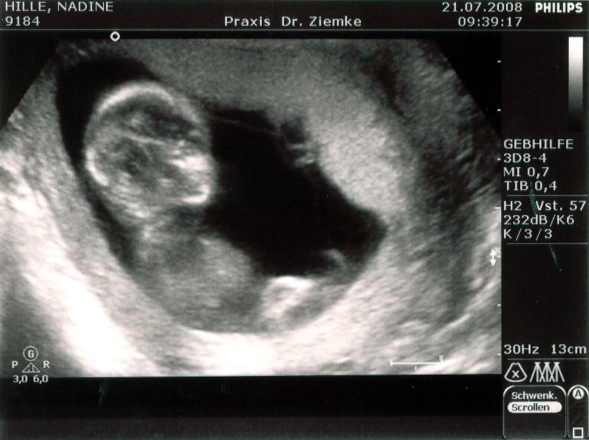

Vorhin waren wir bei Nadins neuer Frauenärztin in der Tuchmacherstraße – Annika Stellmacher heißt die. Und die schreibt nun die Fortsetzung von Nadins Mutterpass. Auf der ersten Seiten des zweiten Teils steht:

21.7. | SSW (LR) 14/4 | SSW korrigiert 13/4

SSL 6,9 | BPD 2,3

Und übersetzt heißt das, dass Nadin nicht in der 15. Schwangerschaftswoche ist, sondern erst in der 14.. Somit verschiebt sich der voraussichtliche Gerburtstermin eine Woche nach hinten – und zwar auf den 22. Januar 2009.

SSL steht für Scheitel-Steiß-Länge, und die beträgt jetzt 6,9 cm.

BPD steht für Biparietaler Durchmesser, und der ist entsprechend 2,3 cm.

Zusammenfassend bedeutet das: Alles in bester Ordnung. Das Herz schlägt, die Anzahl der Finger ist korrekt. Und Mehrlinge werden es auch nicht…